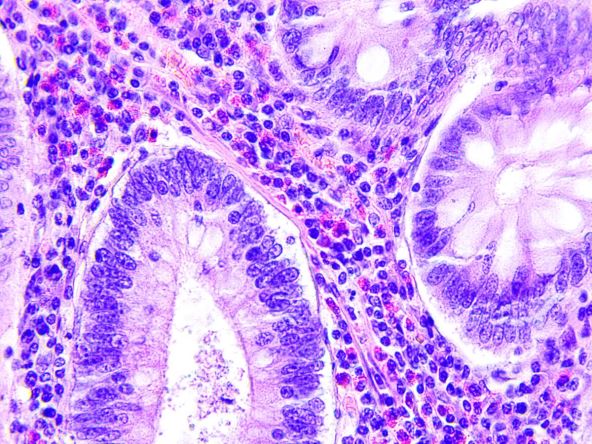

Kolorektalni karcinom pod mikroskopom

Foto: Shutterstock